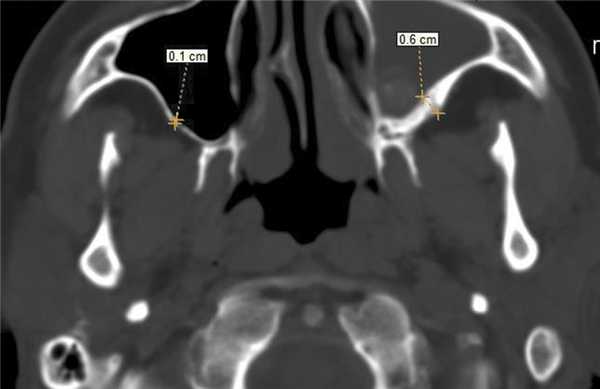

Воспалительные изменения слизистой оболочки верхнечелюстной пазухи, существующие в течение длительного времени, вовлекают в процесс костную стенку. На компьютерных томограммах отмечается утолщение костной стенки в костном режиме и появление «оптического эффекта» — уплотнение стенки в 1,5—3 раза за счет отека надкостницы — при просмотре в мягкотканом режиме (рис. 1, а, б) [9]. При одностороннем процессе, характерном для одонтогенного поражения, на контралатеральной интактной стороне такого эффекта не определяется.

В костном режиме программы просмотра изображений утолщение костных стенок верхнечелюстной пазухи определялось в 21% случаев (рис. 2, 3), что указывает на хронический характер воспаления. «Оптический эффект» в мягкотканном режиме программы просмотра диагностических изображений определялся у 30,7% больных, что указывает на вовлечение надкостницы.

Рис. 2. Рентгеновская компьютерная томограмма околоносовых пазух. Аксиальная проекция, костное окно.

Рис. 3. Рентгеновская компьютерная томограмма околоносовых пазух. Аксиальная проекция, костное окно.

При воспалительных изменениях в ретроантральной жировой клетчатке верхнечелюстной пазухи на РКТ повышаются денситометрические значения ее плотности [10]. При одностороннем процессе отмечается выраженная асимметричность значений плотностей (рис. 4).

Рис. 4. Рентгеновская компьютерная томограмма околоносовых пазух. Аксиальная проекция, костное окно.

В 63,2% случаев на РКТ при выявлении одонтогенного верхнечелюстного синусита отмечалось уплотнение жировой клетчатки. Исследователи связывают это с переходом воспалительной инфильтрации пристеночной слизистой по периваскулярным пространствам к ретромаксиллярной клетчатке [7, 11, 12].